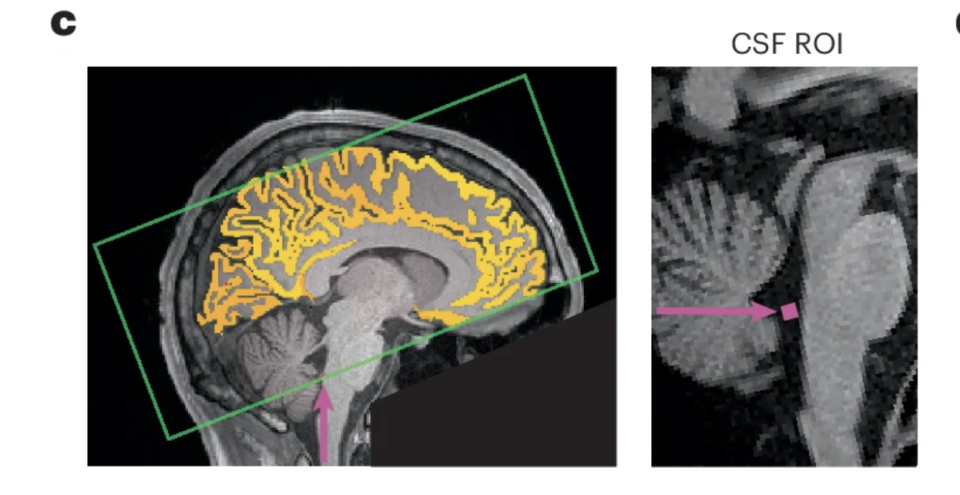

2025 年 10 月发表在《自然神经科学》杂志上的一篇研究指出,熬夜后的注意力不集中,可能是因为你的大脑正在给自己“洗澡”。

脑科学界这几年有个新理论:大脑会在白天产生代谢废物,在睡眠时通过脑脊液不断冲刷、清除掉,从而让大脑再次恢复清洁。

比如大名鼎鼎的大脑代谢废物——阿尔茨海默症的罪魁祸首——淀粉样蛋白,就是在这个过程中被清除干净的。

正常情况下,脑子会在深度睡眠时清除掉代谢废物,但熬夜没睡够,大脑又不能放着不洗,那就只能“白天上班时偷偷洗澡”了。

研究人员找来了 26 位成年人,让他们在一次实验中睡得很好,另一次则整晚不睡。不出意外,熬夜的那次,简单的注意力测试表现很差。

有趣的是,通过脑部 MRI 扫描发现:

每次注意力“断片”的前 2 秒,脑脊液会被冲出脑底;而注意力恢复后的 1 秒,又会被重新吸回大脑。

也就是说,你在发呆、走神的时候,大脑正在进行“紧急冲洗”。

研究者形容:“这就像洗衣机——先加水,再搅动、再排水。注意力走神时,大脑正好在『搅』。

研究人员也说了:睡觉时清理才是最优方案,强行白天补洗,不仅效率低,还直接影响认知表现。